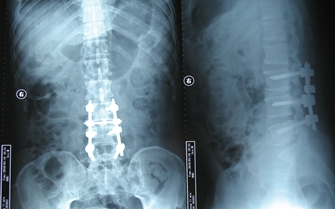

4.人工椎间盘、或腰椎后路椎弓根钉内固定术。

图3.腰椎退变、腰椎间盘突出

图4.腰椎退变、腰椎间盘突出椎弓根钉内固定术后